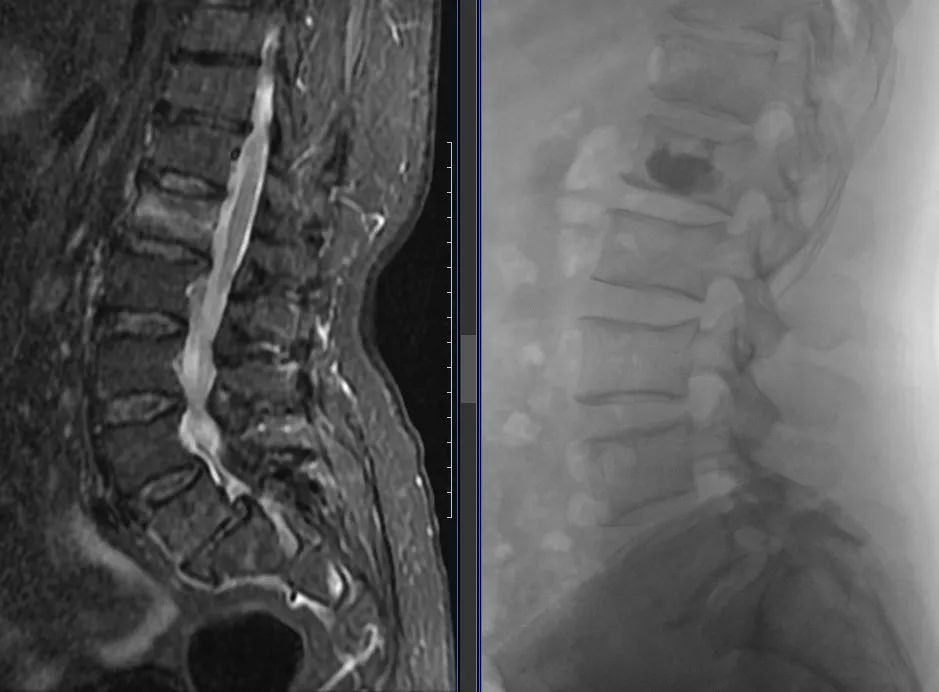

两位老人:白某(94岁,ID:752351)和戴某(93岁,ID:712140),都是因低能量损伤导致胸腰椎骨质疏松性椎体压缩性骨折,受伤后老人因疼痛导致活动严重受限,生活质量下降。由于患者高龄且均患有多种慢性心脑血管及内分泌疾病,快速手术并恢复正常生活迫在眉睫。在家属的充分信任下,骨脊柱科医生为他们实施了胸腰椎骨折椎体后凸成形术,手术效果立竿见影,患者和家属非常满意。

呼和浩特市第一医院骨脊柱科在胡继平主任的带领下,科室医生规范化、标准化开展椎体强化手术(PKP或PVP),每年采用该术式治疗骨质疏松性脊柱椎体压缩骨折近百例。高龄患者已经不再被视为手术的绝对禁忌,在快速康复(ERAS)理念的指导下,可使患者在入院后24小时内完成术前检查,术后次日佩戴支具下地活动,住院日3~5天,取得了良好的手术效果,助力患者尽快恢复正常生活。